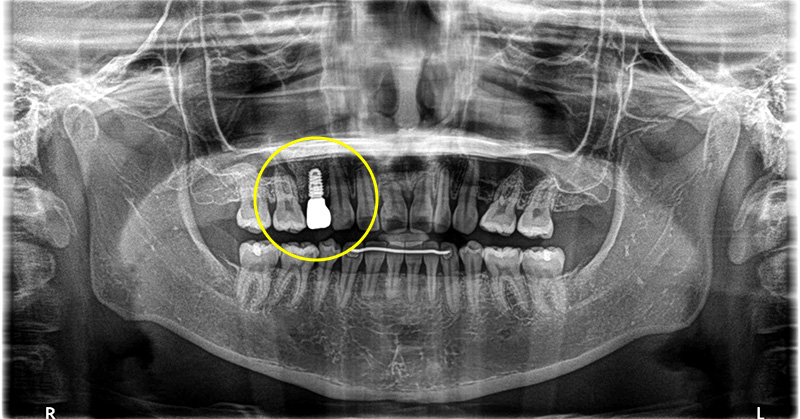

二次オペを行いしっかりとした固定も得られていた為、型取りを2度行い上部に歯を作成しました。

上部構造(人工歯)の装着・治療完了

術後は欠損部位の見た目の改善により、審美的に大変満足していただき、また、機能的な面でも硬いものもしっかり噛むことができ、機能的な面でも大変満足していただきました。

現在は定期的なクリーニングを行うことにより、キレイな状態を保っていただいております。